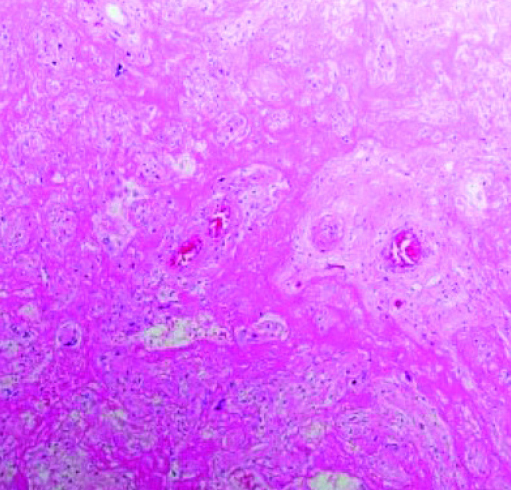

Рисунок 3. Массивное выпадение фибрина.Массивное выпадение фибрина (см. рис. 3) — очень заметный и яркий признак. Иногда ворсины настолько замурованы выпавшим фибрином, что их трудно найти и рассмотреть, циркуляция материнской крови нарушена. Газообмен в плаценте значительно снижается или вовсе прекращается, что ведет к гипоксии и гибели плода.

Рисунки 6, 7. Лимфогистиоцитарный виллит, тромбоз.Лимфогистиоцитарный виллит, тромбоз (см. рис. 6, 7).

В межворсинчатом пространстве видны скопления воспалительного инфильтрата, тромбоз сосудов ворсин, нарушения созревания ворсинчатого хориона.

«Стереотипная реакция плаценты на повреждение — это нарушение созревания. Как по литературным данным, так и на собственном опыте мы с этим сталкивались при подтвержденном COVID-19. В отличие от зрелой плацентарной ткани видна очень рыхлая строма. При выраженном лимфогистиоцитарном виллите, как правило, наблюдается тромбоз сосудов — и крупных, и капилляров».

Сканируя гистологические препараты на малом увеличении, мы видели крупные участки тромбоза с массивным выпадением фибрина в межворсинчатом пространстве. На большом увеличении в периферии участков тромбоза наблюдается воспалительная инфильтрация в ворсинах и межворсинчатом пространстве. Можно рассмотреть, как фибрин буквально заклеивает собой ворсины.

В основном это свежий фибрин, хотя наблюдаются и участки более зрелого фибрина. То есть на морфологическом уровне мы предполагаем, что поражение плаценты происходит достаточно быстро и ведет к гибели плода. Все это подтверждается и клиническими данными.